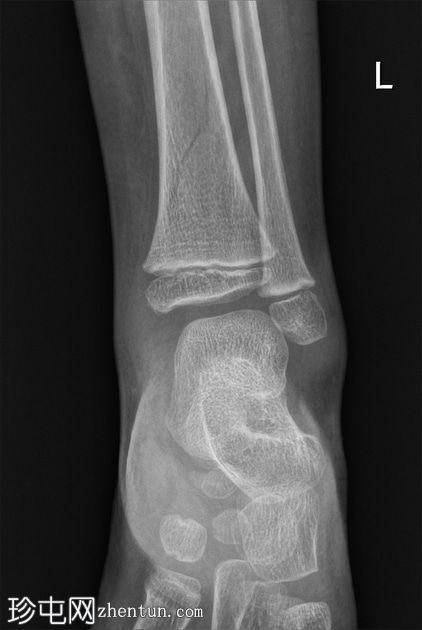

左腿及踝关节

X线片

正位

胫骨远端骨干可见一条螺旋状透亮线,提示骨折(正位、侧位)。

应用锐化算法并放大正位片(骨折由近端向远端)和侧位片。

幼儿骨折是指幼儿因扭转(足部着地时股骨内旋)导致的胫骨中远端轻微移位的螺旋状骨折,这种情况可能发生在儿童绊倒时。患者接受了6周的石膏外固定治疗。

请注意,应用锐化骨算法并放大图像后,骨折及其范围会更加清晰可见。